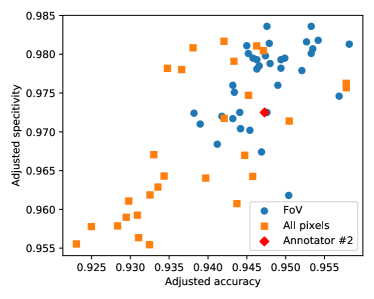

In some papers (such as (Wu et al., 2020)), multiple triplets of aggregated scores are reported to illustrate the effects of the various steps of the proposed methods. Similarly to the image level analysis, the majority rule is applied to make clear decisions about the region of evaluation used by the authors. The results are summarized in Table 3 and plotted in Figure 5. Again, we assigned 3 labels to the papers, in 30 cases the use of the FoV was accepted, in 18 cases the use of all pixels was accepted, and 16 papers were classified as outliers (the scores do not pass the test with either of the hypothesised regions). As before, the ranking in Table 3 and the illustration in Figure 5 confirm the expected bias in the evaluations: the algorithms evaluated on all pixels tend to have higher accuracy and specificity scores, in general.

In Figure 6 we have plotted the distribution of algorithms and evaluation methodologies in the adjusted accuracy-specificity plane. The plot shows that after eliminating the bias, the algorithms evaluated with all pixels have lower accuracy and specificity scores than those evaluated with the FoV mask. The independent two-sample t-test shows that the difference is statistically significant with a p-value of . The reason for this surprising phenomenon is that using all pixels to evaluate less effective techniques results in performance scores comparable to or even higher than those of more effective techniques evaluated under the FoV mask, and this brings publicity to less effective approaches.

Finally, we compare the performances of the methods by their operating principles. We have introduced 4 categories: deep learning, classical (thresholding, filtering, morphology, region growing), supervised (feature extraction and supervised machine learning, but not deep learning), and others (dominantly graph-cut based segmentation techniques). The results presented in Figure 6 show that deep learning techniques increase the accuracy by almost 1% compared to the best performing classical and supervised techniques.